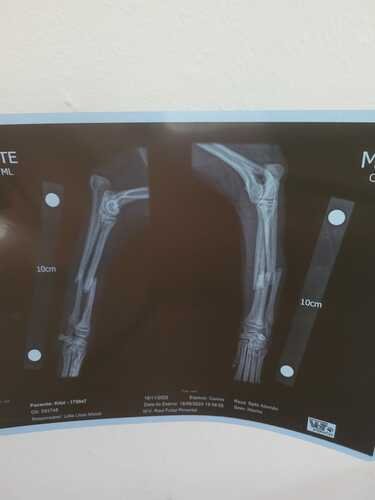

Este é o Kilate, este neném sofreu uma fratura e os antigos donos optaram por doá-lo. Agora estamos em mais uma tentativa de resgate e ajuda aos animais, para que ele seja operado e se recupere o mais rápido possível, para que ache um novo lar cheio de amor